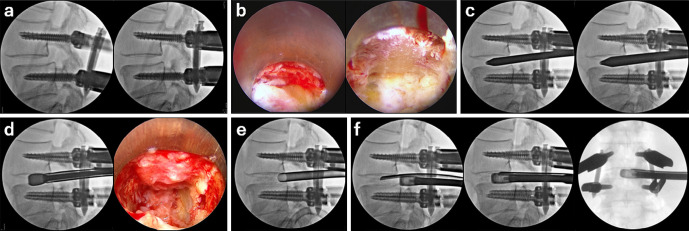

前言:比较采用经皮内镜下经椎间孔腰椎椎间融合术(PETLIF)系统的全内镜下经椎间孔入路腰椎椎间融合术(TF-LIF)和微创经椎间孔腰椎椎间融合术(MIS-TLIF)的临床结果。方法:共102例患者,其中女性80例,男性22例;平均年龄:70.0岁)的退行性腰椎疾病患者接受PETLIF治疗并随访2年,被分配到PETLIF组。根据PETLIF组的年龄、性别和手术腰椎水平,100例患者(71例女性,29例男性;随机选择接受MIS-TLIF的患者纳入MIS-TLIF组,平均年龄68.9岁。这项回顾性调查包括手术资料、影像学评估和临床结果。结果:PETLIF组和MIS-TLIF组融合率分别为95.1%和96.0% (P=0.38)。PETLIF组术前至术后1天血红蛋白水平的下降明显低于MIS-TLIF组(ppp)结论:与MIS-TLIF相比,PETLIF具有良好的骨融合率和临床效果。它是微创的,导致较少的失血。然而,出神经根损伤是petlifs特有的并发症,需要适当的预防管理,包括扩大Kambin三角区的技术。

Methods: A total of 102 patients (80 females, 22 males; mean age: 70.0 years) with degenerative lumbar spine disorders who underwent PETLIF and were followed up for 2 years were assigned to the PETLIF group. Based on age, sex, and operated lumbar levels in the PETLIF group, 100 patients (71 women and 29 men; mean age: 68.9 years) who underwent MIS-TLIF were randomly selected and included in the MIS-TLIF group. This retrospective investigation included surgical data, radiographic assessment, and clinical outcomes.

Results: The fusion rate was 95.1% and 96.0% in the PETLIF and MIS-TLIF groups, respectively (P=0.38). The decrease in hemoglobin levels from before surgery to 1 day after surgery was significantly lower in the PETLIF group than in the MIS-TLIF group (P<0.01). Five patients had detectable transient neurologic disorders after PETLIF that were resolved within 3 months. The increase in the local lordosis angle from before surgery to the final follow-up was significantly higher in the MIS-TLIF group than in the PETLIF group (P<0.01). Clinical scores were comparable between the two groups.

Conclusions: Compared with MIS-TLIF, PETLIF showed excellent bone fusion rate and clinical outcomes. It was minimally invasive, resulting in less blood loss. However, exiting nerve root injury was a PETLIF-specific complication, and proper preventive management, including techniques to enlarge the Kambin's triangle, is required.